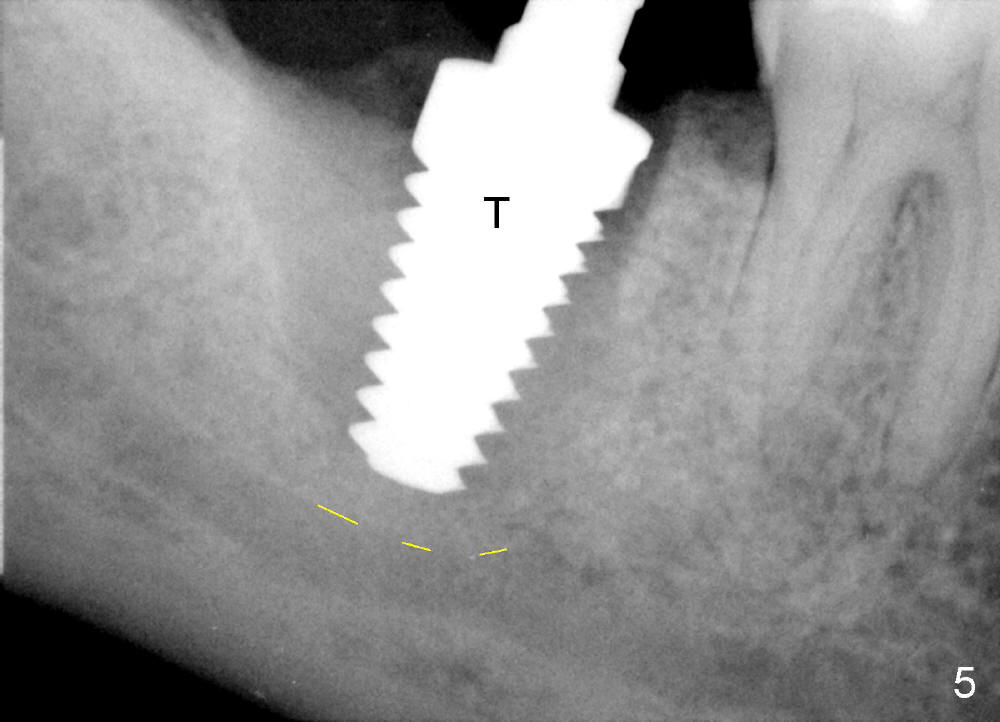

The tooth #31 of a 38-year-old lady has endo perio disease (Fig.1). Due to the large periapical lesion, there will be no solid (new) bone available for primary stability of an immediate implant (Fig.2: 7x17 mm). Yellow dashed line represents the upper border of the Inferior Alveolar Canal (IAC). Infiltration anesthesia is administered first. The mesiodistal widths of the root of the extracted tooth are 10 and 7 mm at the coronal and apical ends, respectively; the buccolingual ones 7 and 5 mm; the length 17 mm (Fig.3). The socket appears much larger than the root (Fig.4). To prevent paresthesia, no drills are used. Instead, a series of tap drills (6,7,8x17 mm) are sequentially inserted into the socket. The largest tap (Fig.5 T; 8x17 mm) binds to the socket securely with separation from IAC. Block anesthesia has to be administered before removal of the tap. A tapered implant (8x17 mm) is placed with insertion torque greater than 60 Ncm (Fig.6 I); allograft mixed with Osteogen is placed around the implant (*). Collagen dressing covers the opening of the remaining socket. The wound is protected with perio dressing, which is partially secured by an abutment (A in Fig.6). No paresthesia is reported by the patient a few hours postop.

The gingiva forms a band (cuff) around the implant (Fig.11 *) and bone has apparently filled the peri-implant gap (Fig.13 *) 3.5 months postop. The gingival cuff is present immediately pre-crown cementation (Fig.12 *). The bone density around the implant continues to increase 2 and 7 months post cementation (Fig.14,15), in spite of retention of residual cement distally (<).